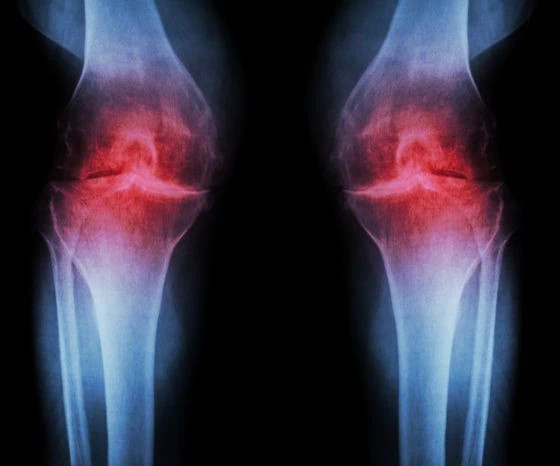

Nivelrikko on yksi yleisimmistä nivelvaivoista. Se voi aiheuttaa kipua, jäykkyyttä ja liikkuvuuden heikkenemistä erityisesti polvissa, lonkissa, sormissa, niskassa ja alaselässä.

Nivelrikkoa esiintyy yleisimmin polvissa, lonkissa, sormissa ja selkärangan nivelissä.

Polvi:

Polven nivelrikko aiheuttaa usein kipua kävellessä, portaissa ja pitkän seisomisen jälkeen. Polvi voi tuntua jäykältä erityisesti aamuisin tai istumisen jälkeen liikkeelle lähtiessä.